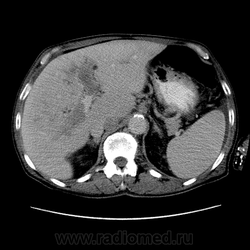

Здравствуйте, коллеги! Мужчина около 70 лет. Жалобы: слабость, утомляемость около 3х месяцев, чувство тяжести на желудке после еды. Анамнез: онко не было. С вышеописанными жалобами обратился ко врачу, сделали ФГЭДС - признаки гастродуоденита, по биопсии - N. В течение 2х последних недель существенно похудел и начал желтеть. Выполнена МСКТ

А как насчет холангиокарциномы с тромбозом воротной вены и мтс в средостение, лимфоузлы брюшной полости и забрюшинного пр-ва?

Внимательно пересмотрел, признаков характерных для ГЦР не нашел (кроме тромбоза). Согласен с холангиокарциномой, ещё бы отсроченную фазу, для печени минут через 12-15 .

1. Гиперденсивность, в артериальную фазу  всей опухолевой массы (опухоль хорошо васкуляризирована)

2. Гиподенсивность, в портальную фазу (быстрое вымивание, опять же обусловлено васкуляризацией)

3.Тромбоз портальной вены.

Для холангиокарциномы характерно гиперденсивность, в отсроченную фазу, за счет аффинитета к контрастному веществу.

Внесу лепту: видел пару гистологически подтверждённых ХЦР в периферических отделах правой доли, естественно без расширения протоков, одна прорастала диафрагму и метастазировала в узлы ворот, вторая прорастала сегментарные сосуды, вызывая атрофию двух кажется сегментов. На мрт выглядели примерно одинаково: большой солидный периферический компонент, быстро интенсивно накапливающий контраст. На отсроченных томограммах - вымывание контраста из периферической части и накопление в центральной зоне распада. ГЦР вроде и гиповаскулярный бывает, самому не встречался правда.